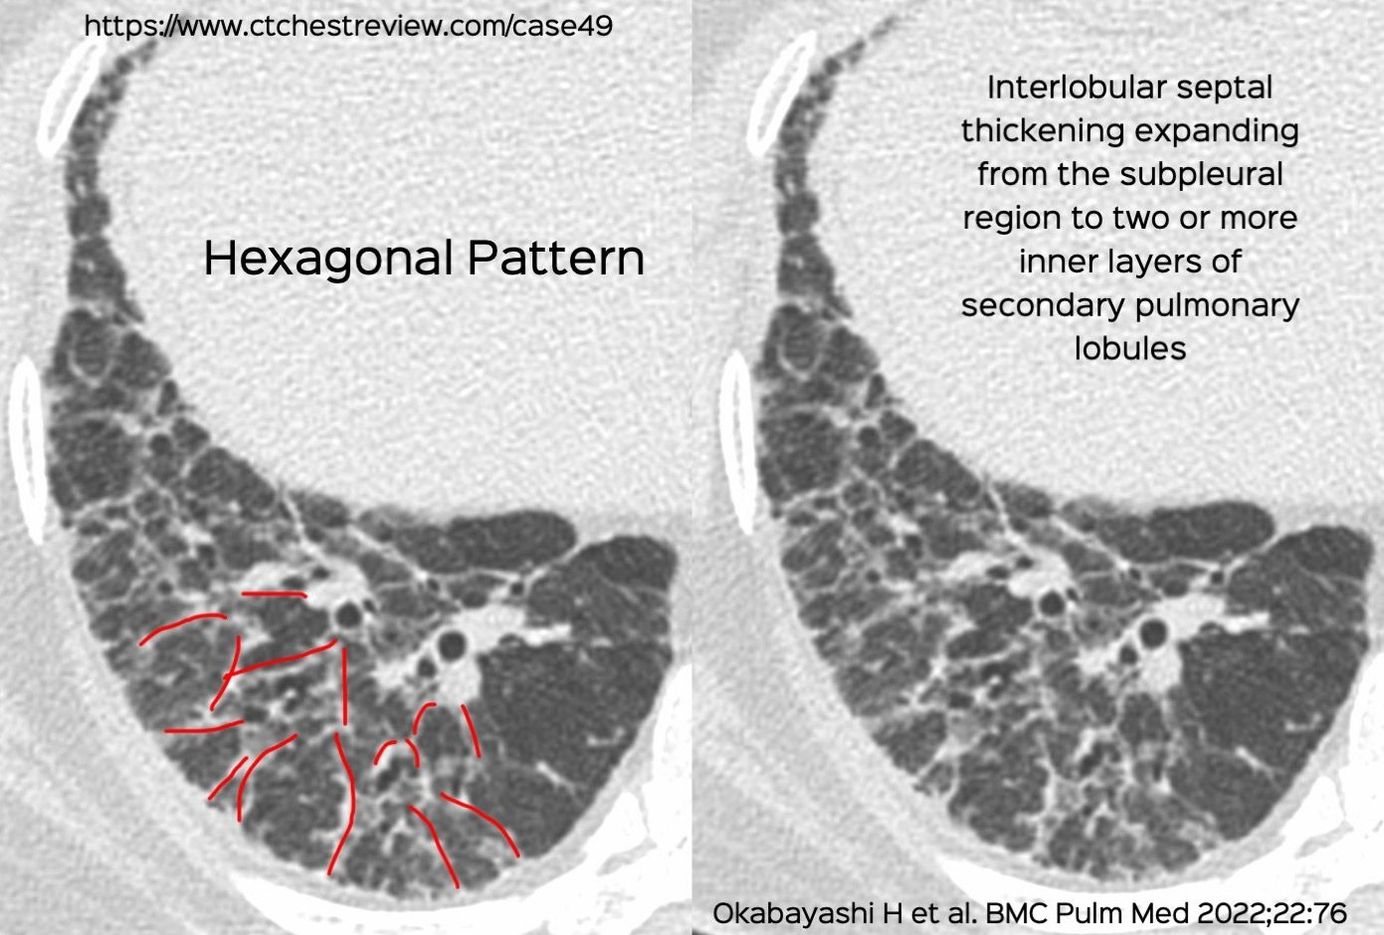

Case 49: The Hexagonal Pattern in Fibrotic Hypersensitivity Pneumonitis Members Public

The hexagonal pattern described the presence of confluent perilobular fibrosis in patients with fibrotic hypersensitivity pneumonitis